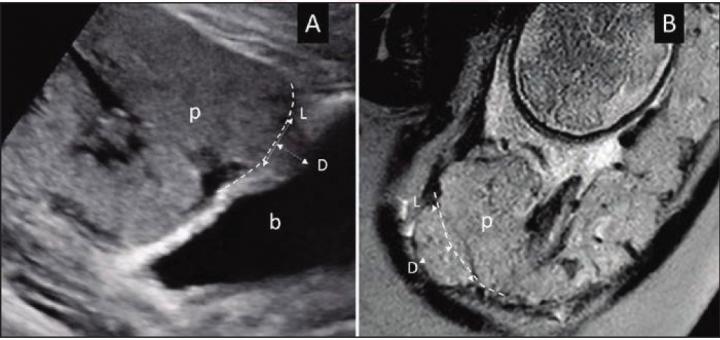

image: (A) Ultrasound in 28-year-old woman (B) MRI in 34-year-old woman with suspected PAS disorder. Focal area of placental tissues bulge toward imaginary lines of normal uterine contour (dash lines). Length (L) and depth (D) measurements of placental bulge also demonstrated. p = placenta; b = bladder.

On ultrasound and MRI alike, the placental bulge sign represents deeper venous invasion in PAS--the focal area of myometrial-placental bulging beyond the normal uterine contour. Dighe and colleagues' retrospective study included 62 pregnant women (mean age, 33.2 years) with clinically suspected PAS who underwent both ultrasound and MRI. Blinded to final diagnoses, two maternal-fetal medicine specialists for ultrasound and three abdominal radiologists for MRI independently reviewed images for their respective modality. Using intraoperative and pathologic findings, alongside International Federation of Gynaecology and Obstetrics classification, patients were separated into those with and without severe PAS.

"In diagnosing severe PAS," Dighe et al. noted, "placental bulge sign achieved on ultrasound an accuracy of 85.5%, sensitivity of 91.7%, and specificity of 76.9%, and on MRI an accuracy of 90.3%, sensitivity of 94.4%, and specificity of 84.6%." Ultimately, placental bulge was an independent predictor of severe PAS on ultrasound (odds ratio=8.94) and MRI (odds ratio=45.67).